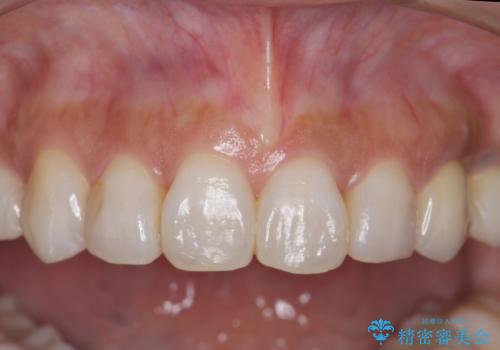

終了時

左:虫歯を除去したところ。遠心が歯ぐきより深い状態です。中:そのままかぶせようとすると、遠心が歯ぐきが腫れやすい状態です。右:エクストリュージョンをしたことで、遠心の歯ぐきの腫れが収まっていることがわかります。

治療について

エクストリュージョンをしたことで、いくら歯磨きを頑張ってもどうしても腫れてしまう歯肉に対して、歯周囲組織の位置関係を変えることで根本的に解決しました。

今回は、単独1歯のエクストリュージョンを、マウスピースを使って、ご自身でゴムをかけていただき行ったのがポイントです。

歯の変色もあるため、最終的にはクラウンとしました。